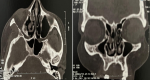

Investigations: tomodensitométrie naso-sinusienne: pneumatisation massive du cornet moyen droit, compression du complexe ostéoméatal, sans lésion osseuse destructrice (Figure 2).

Figure 2: coupe axiale et coronnale d'une tomodensitométrie naso-sinusienne montrant la pneumatisation massive du cornet moyen droit